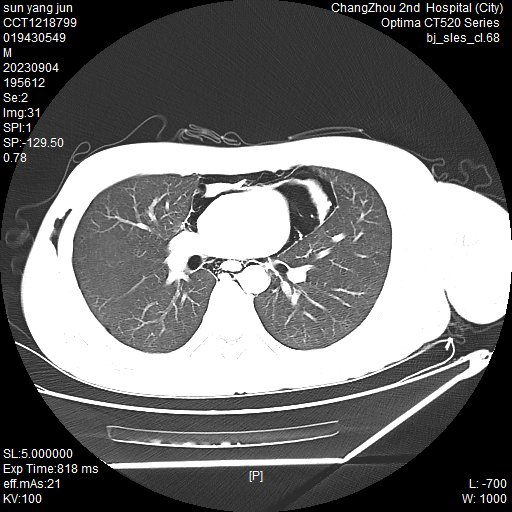

据悉,就诊过程中,这两个小伙子手捂胸口,神情痛苦,都有不同程度的疼痛感,通过胸部 CT 检查,医生告知这是出现了纵隔气肿。

常州二院胸心外科主任吴奇勇科普:「纵隔是左右纵隔胸膜之间的器官结构和结缔组织,而纵隔气肿则是在没有外伤、病菌感染、邻近脏器损伤的情况下,空气异常进入纵隔胸膜内结缔组织间隙之间,导致患者出现胸痛、干咳、呼吸困难、颈部吞咽困难等症状。纵隔气肿不仅会出现疼痛,还会出现皮下气肿。最常见的部位为颈部皮肤肿胀,也可发生面部、肩部等,触摸肿胀部位时,感觉像是握雪球的感觉,医学上称为『握雪感』。对于纵隔气肿这个疾病,胸部 CT 无疑是最快、最有效的辅助检查。值得特别注意的是,自发性纵隔气肿导致纵隔内压力上升,对心脏和大血管产生压迫,容易引发心衰,也可能引发严重的纵隔感染,这些都有可能危及生命。」